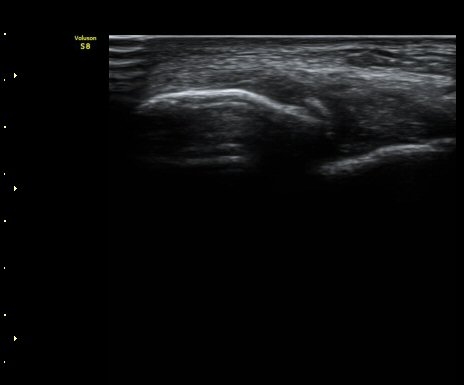

ÃÊÀ½ÆÄ °Ë»ç

ÃÊÀ½ÆÄ °Ë»ç ½Ã ¹ß¸ñ °üÀýÀÇ ¼ö¾×Àú·ù°¡ °üÂûµÊ(±×¸² 1).